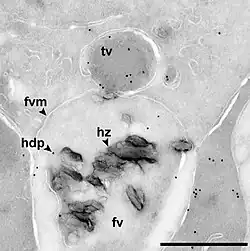

The malaria parasite, therefore, detoxifies the hematin, which it does by biocrystallization—converting it into insoluble and chemically inert β-hematin crystals (called hemozoin).[13][14][15] In Plasmodium the food vacuole fills with hemozoin crystals, which are about 100–200 nanometres long and each contain about 80,000 heme molecules.[4] Detoxification through biocrystallization is distinct from the detoxification process in mammals, where an enzyme called heme oxygenase instead breaks excess heme into biliverdin, iron, and carbon monoxide.[16]

Several mechanisms have been proposed for the production of hemozoin in Plasmodium, and the area is highly controversial, with membrane lipids,[17][18] histidine-rich proteins,[19] or even a combination of the two,[20] being proposed to catalyse the formation of hemozoin. Other authors have described a heme detoxification protein, which is claimed to be more potent than either lipids or histidine-rich proteins.[12] It is possible that many processes contribute to the formation of hemozoin.[21] The formation of hemozoin in other blood-feeding organisms is not as well-studied as in Plasmodium.[22] However, studies on Schistosoma mansoni have revealed that this parasitic worm produces large amounts of hemozoin during its growth in the human bloodstream. Although the shapes of the crystals are different from those produced by malaria parasites,[23] chemical analysis of the pigment showed that it is made of hemozoin.[24][25] In a similar manner, the crystals formed in the gut of the kissing bug Rhodnius prolixus during digestion of the blood meal also have a unique shape, but are composed of hemozoin.[26] Hz formation in R. prolixus midgut occurs at physiologically relevant physico-chemical conditions and lipids play an important role in heme biocrystallization. Autocatalytic heme crystallization to Hz is revealed to be an inefficient process and this conversion is further reduced as the Hz concentration increases.[27]